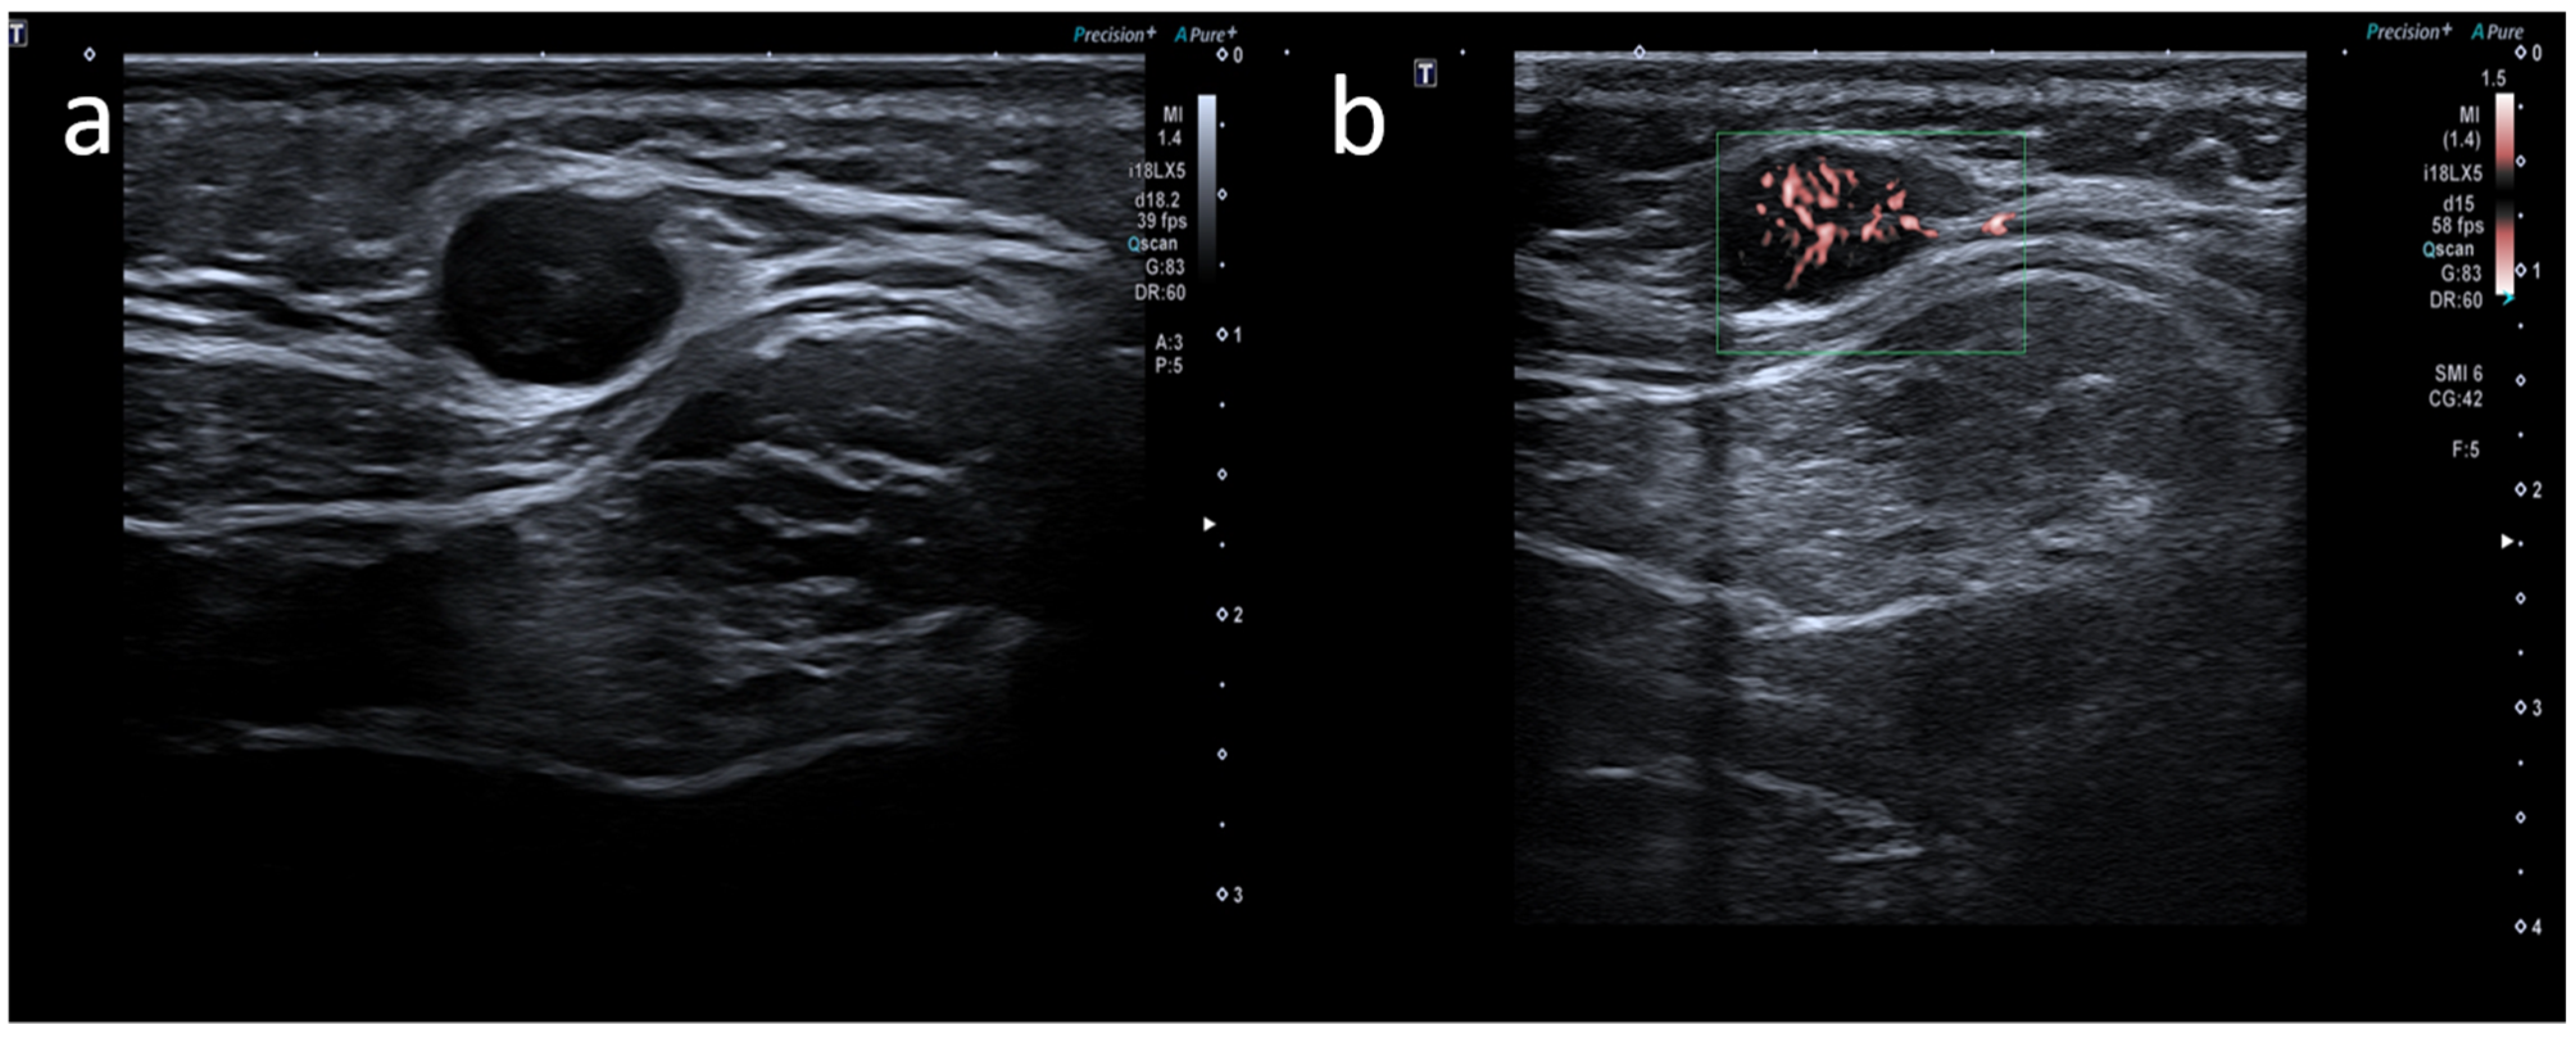

- Cocco, G.; Pizzi, A.D.; Fabiani, S.; Cocco, N.; Boccatonda, A.; Frisone, A.; Scarano, A.; Schiavone, C. Lymphadenopathy after the Anti-COVID-19 Vaccine: Multiparametric Ultrasound Findings. Biology 2021, 10, 652. [Google Scholar] [CrossRef] [PubMed]